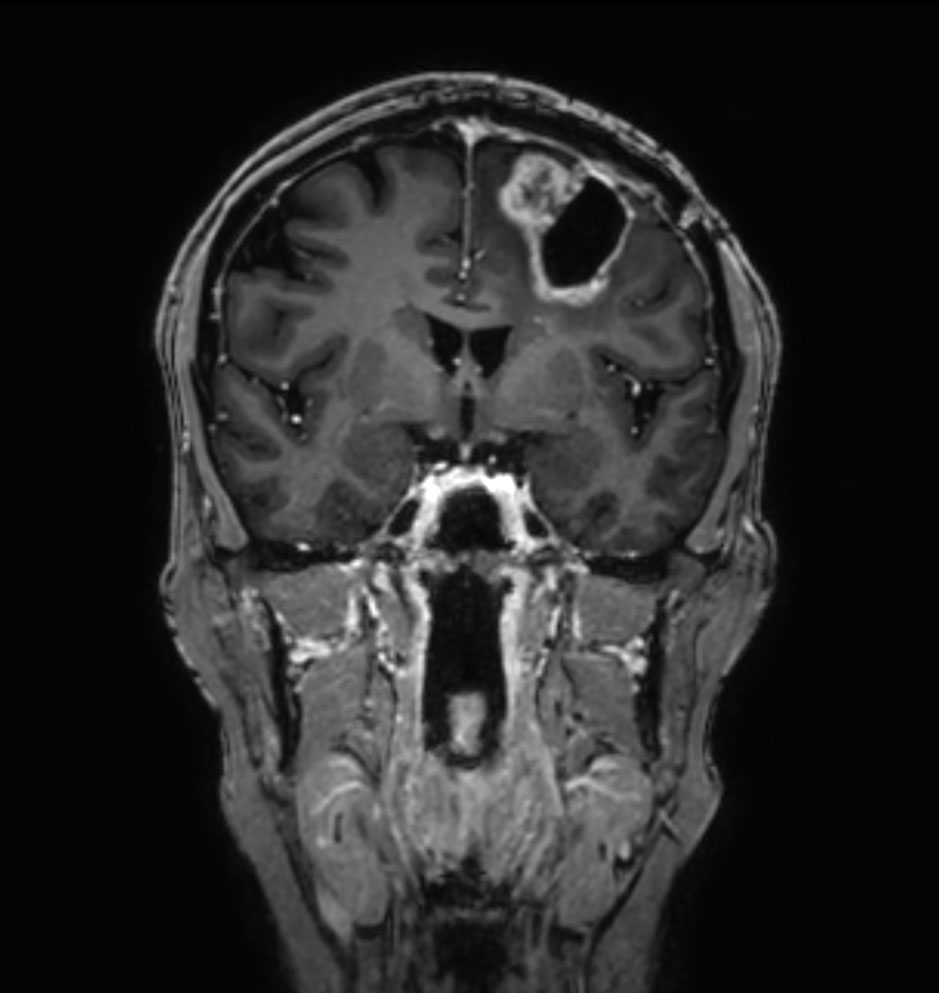

3D T1w TFE - Coronal reformat

3D T1w TFE - Coronal reformat (with gado)